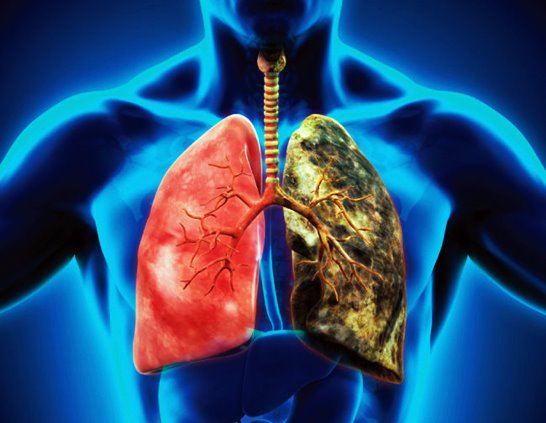

폐암 초기증상은 호흡관란, 지속적인 기침 및 가래, 흉통 등이 있으며, 조기발견과 정확한 진단이 중요합니다. 아래에서는 폐암 초기증상에 대해 자세히 알아보고 조기 발견할 수 있도록 도움이 되었으면 합니다.

폐암 예방법

흡연은 폐암의 가장 큰 원인 중 하나입니다. 담배를 피우지 않거나 금연하는 것이 폐암 예방에 가장 효과적입니다. 만약 흡연 중이라면 의사나 금연 전문가의 도움을 받아 금연 계획을 수립하는 것이 좋습니다.